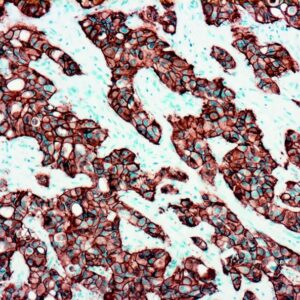

The fluoresceinated Hsa-miR-365A-3P probe has been designed from mature human miR-365A-3P sequence. This Hsa-miR-365A-3P identifies miR-365A-3P sequences in formalin-fixed, paraffin-embedded human tissues and freshly prepared frozen tissues by in situ hybridization. This probe does not react with normal human mRNA or nuclear DNA present in tissues.